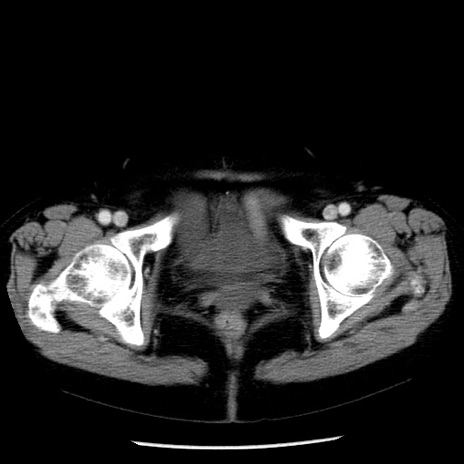

冠状断像

【症例】70歳代女性

【主訴】腹痛、嘔吐

【現病歴】15時間程前(昨晩)より腹痛あり。今朝になっても症状の改善なく、嘔吐あり。腹痛も増悪あり、救急外来受診。

【既往歴】子宮癌全摘術後

【身体所見】意識清明、BP 121/72mmHg、P 74bpm、SpO2 100%(RA)、腹部:平坦・軟、腸雑音ほぼ聴取せず。下腹部・心窩部・臍左上に圧痛あり。反跳痛なし。

【データ】WBC 10600、CRP 0.15